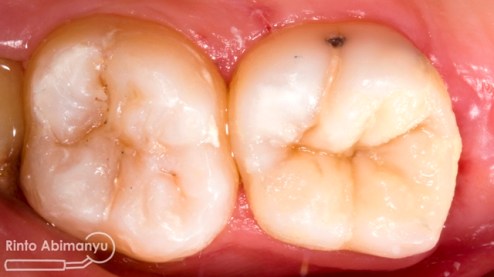

Sebagai basis digunakan low shrinkage stress flowable composite SDR (Dentsply) dan diatasnya memakai Z350XT (3M)…

Alhamdulillah dari foto ronsen terlihat pengisian sepanjang kerja dan hermetis, tambalan di bagian mahkota juga terlihat rapat dan homogen….